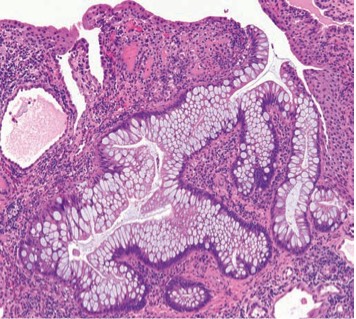

1017. У мужчины 60 лет слизистая мочевого пузыря с неровными узловыми возвышениями, предположительным диагнозом, основываясь на изменениях, приведенных на микрофотографии, будет